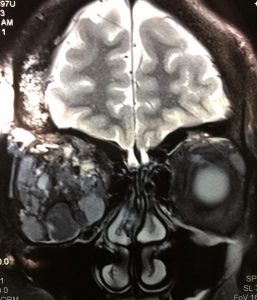

Tumores Orbitários

Os pacientes com TUMORES ORBITÁRIOS, benignos ou malignos, recebem de nossa equipe uma atenção especial. É um campo da Oculoplástica que nos dedicamos com afinco. Acometem crianças e adultos. São incomuns, mas quando aparecem podem colocar a visão em risco. Eventualmente se estendem para o sistema nervoso ou se espalham pelo corpo. Alguns são operáveis, outros são eliminados com radioterapia/quimioterapia. É preciso um estudo diagnóstico minucioso, uma estratégia cirúrgica bem traçada, além de um suporte emocional adequado